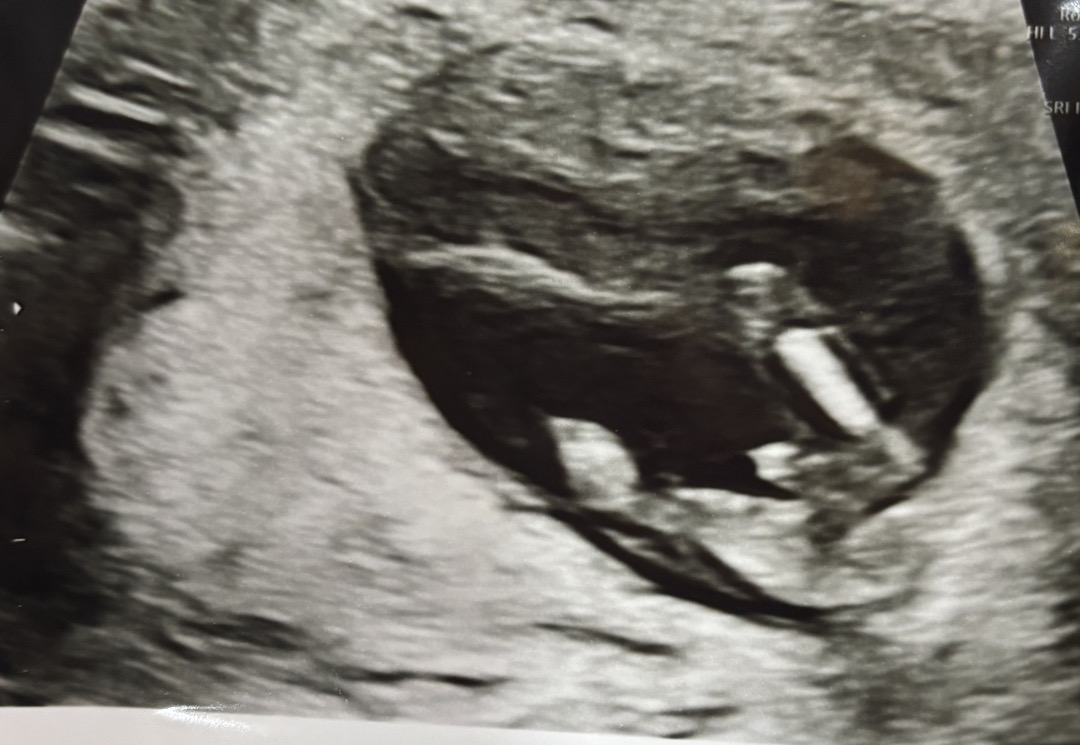

13주0일차 성별 이렇게 잘 보일수있나요..?

이게 하반신사진만 따로 찍은건데 정확한 성별은 16주때 알 수 있다고 들었거든요! 근데 오늘 초음파보는데.. 너무 똭 나타나서 의사샘이랑 같이 놀랬어요 ㅋㅋㅋ큐ㅠㅠ 이정도면 거의 확정인가요..?반전되진 않겠죠..?ㅎ

헝 ㅠㅠ귀여워요..아들이라고 확실하게 알려주고있는 ㅎㅎ